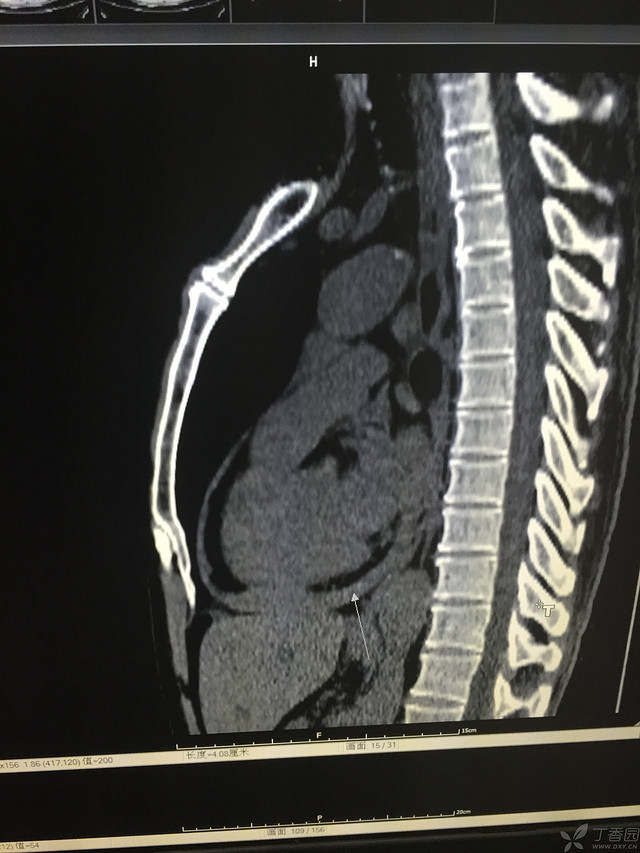

患者性别:男

患者年龄:64岁

简要病史:三天前休息时突发胸前区疼痛伴大汗,到当地医院输液治疗后缓解,3小时前情绪激动后再次出现胸痛伴大汗,胸部压迫感,持续不缓解入院,到当地医院测血压180/?mmHg泵入硝酸甘油转入我院。

体格检查:血压94/72mmHg(右侧)96/74mmHg(左侧),心率78此/分,其他未见阳性体征